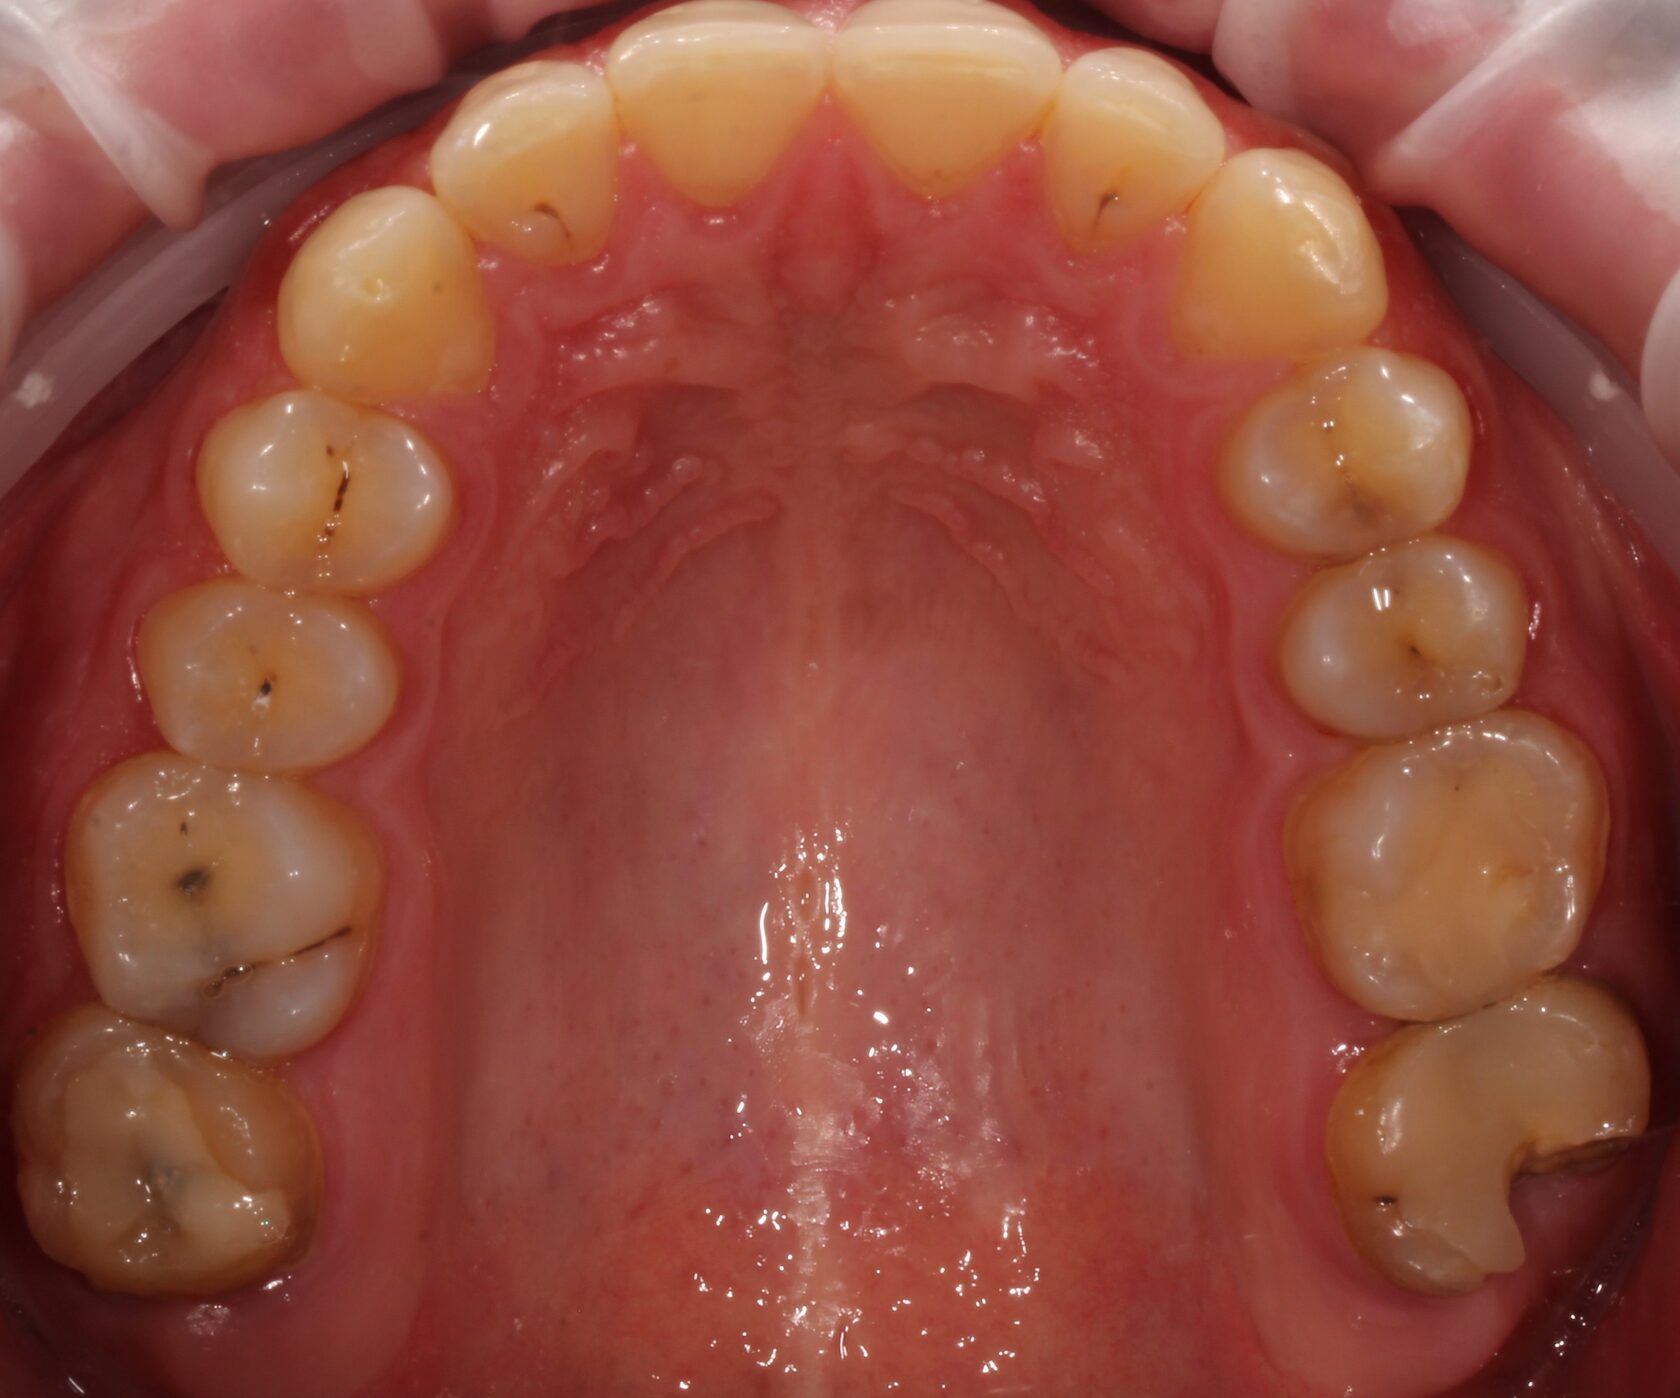

Результат комплексного лечения пациента командой врачей нашей клиники.

Выполнено:

1 Комплексная диагностика и планирование лечения.

2 Лечение всех зубов пораженных кариозным процессом и замена всех несостоятельных пломб.

3 Удаление зубов мудрости.

4 Установка дентальных имплантатов в зоны удаленных зубов.

5 Финальное рациональное протезирование с опорой на дентальные имплантаты.

6 Динамическое наблюдение с 2022 года.